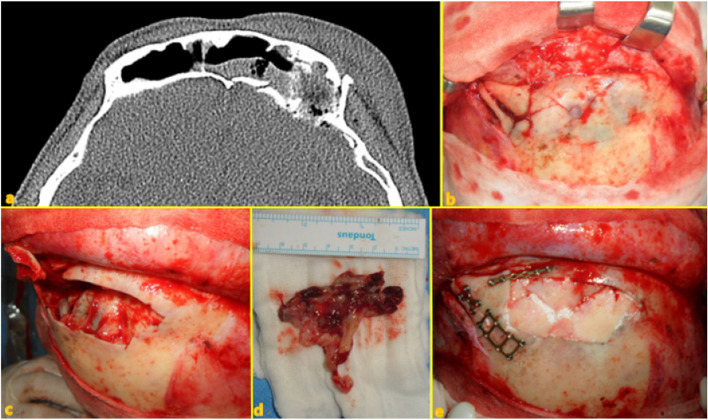

Background: Frontal sinus injuries are relatively rare among facial bone traumas. Without proper treatment, they can lead to fatal intracranial complications, including meningitis or brain abscesses, as well as aesthetic and functional sequelae. The management of frontal sinus injuries remains controversial, with various treatment methods and outcomes being reported. This article describes the clinical characteristics, surgical methods, and outcomes among 17 patients who underwent surgery for frontal sinus injury and related complications.

Case presentation: We retrospectively included 17 patients who underwent surgery for frontal sinus injury and its related complications at the Kangwon National University Hospital between July 2010 and September 2021. Among them, six underwent simple open reduction and fixation of the anterior wall, eight underwent sinus obliteration, and three underwent cranialization. Two patients who underwent sinus obliteration died due to infection-related complications. The patient who underwent cranialization reported experiencing chronic headache and expressed dissatisfaction regarding the esthetic outcomes of the forehead. Except for these three patients, the other patients achieved satisfactory esthetic and functional recovery.

Conclusion: Active surgical management of frontal sinus injuries is often required owing to the various complications caused by these injuries; however, several factors, including the fracture type, clinical presentation, related craniomaxillofacial injury, and medical history, should be considered while formulating the treatment plan. Surgical treatment through the opening of the frontal sinus should be actively considered in patients with severely damaged posterior wall fractures and those at risk of developing infection.